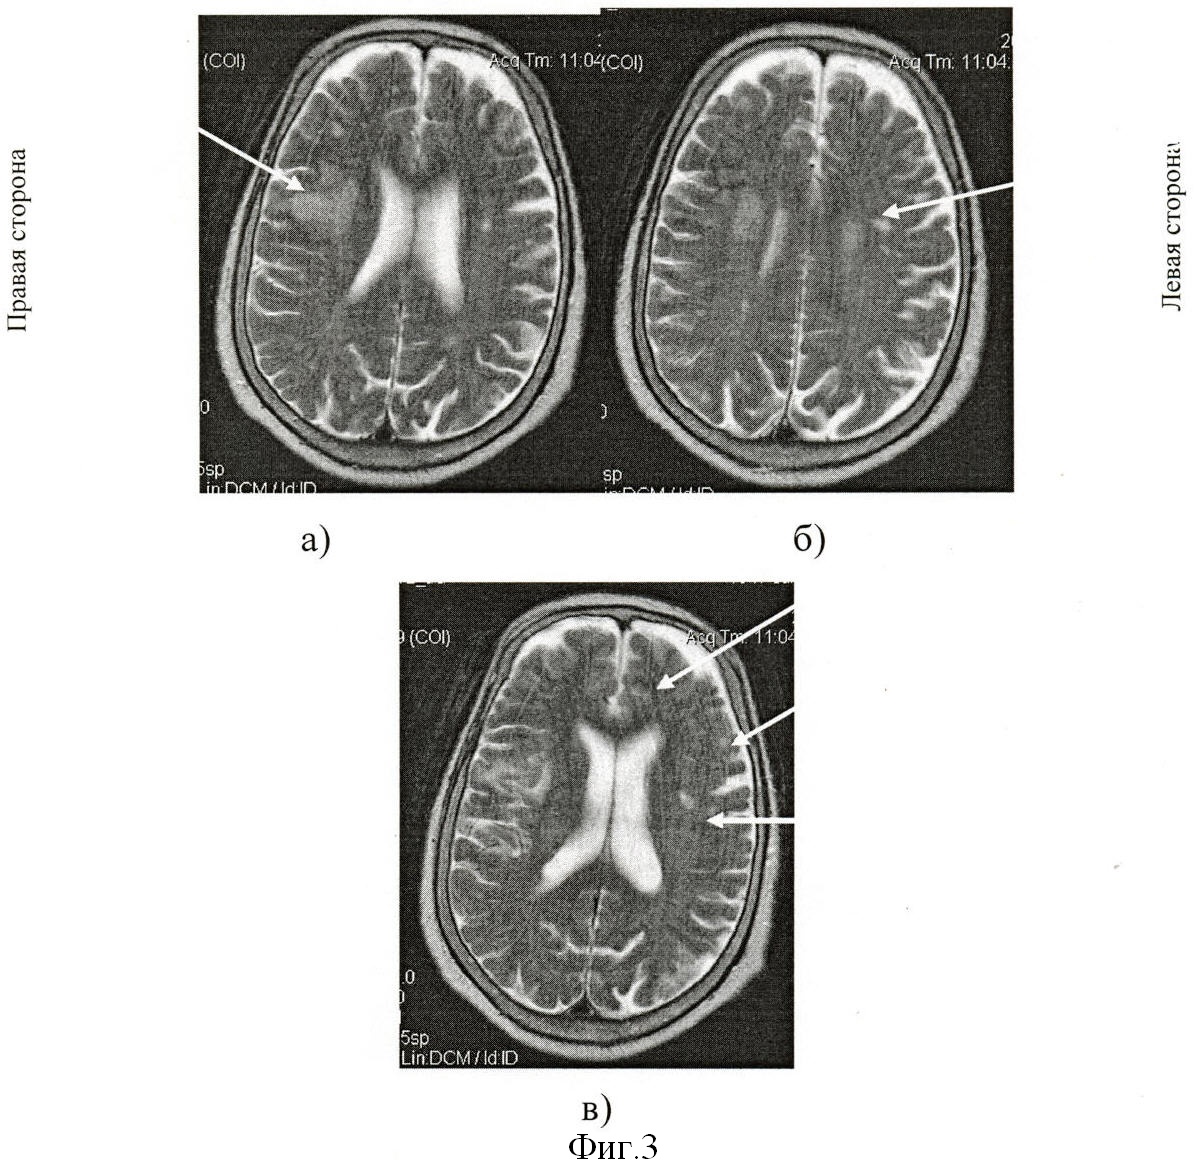

Визуально при магнитно-резонансной томографии выявили: округлая зона (фиг.1а) острого нарушения мозгового кровообращения по ишемическому типу в области таламуса слева размером 2,4×1,4×2,2 см; постишемическая клиновидная киста (фиг.1б) в субкортикальных отделах теменно-височно-затылочной области справа размером 7,3×4,6×6,1 см и множественные мелкие постишемические очаги (фиг.1в) в белом веществе субкортикальных и перивентрикулярных отделов лобных, теменных долей размерами до 0,8 см. Определили наличие смешанной заместительной гидроцефалии. Отметили многоочаговость и асимметричность поражения церебральных структур с локализацией очагов как в базальных отделах, так и субкортикальных зонах обоих полушарий мозга.

С экрана дисплея вычислили реальные величины линейных параметров на трех последовательных срезах, начиная с уровня базальных ганглиев, таламуса и выше. На уровне базальных ядер таламуса определили максимальную ширину сильвиевых борозд справа (20 мм) на фиг.2а и слева (14 мм) на фиг.2а; на уровне визуализации сосудистых сплетений желудочков головного мозга – ширину задних рогов боковых желудочков справа (15 мм) на фиг.2б и слева (12 мм) на фиг.2б и максимальное расстояние между внутренними пластинками костей черепа (150 мм) на фиг.2б; на уровне центральных частей боковых желудочков – минимальную ширину правого (14 мм) на фиг.2в и левого (15 мм) на фиг.2в тел боковых желудочков. Дополнительно рассчитали суммарный когнитивный индекс по предложенной формуле: СКИ=(20+14+15+12+14+15)/150=0,6. Сопоставили вычисленный индекс, равный 0,6, с его критическим значением 0,44. Вычисленный индекс выше значения 0,44, значит прогнозируем развитие постинсультной деменции. И действительно, на 21-ые сутки болезни осмотрен психиатром в связи с расстройствами памяти и мышления, затруднениями в выполнении навыков самообслуживания при регрессе неврологической симптоматики до рефлекторного центрального правостороннего гемипареза. Заключение психиатра: признаки сосудистой деменции с грубым нарушением самообслуживания.